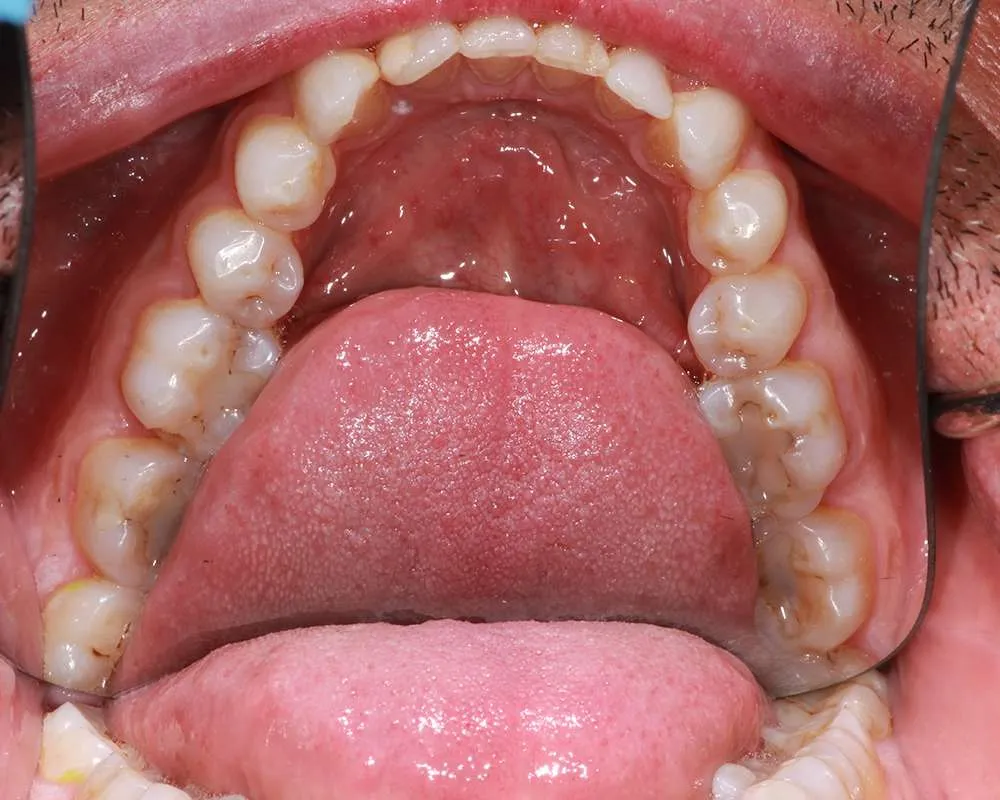

Real Stories, Real Results: Case Studies Showcasing How Our Personalized Approach Transforms Smiles and Lives

Complex Cases

Witness the Remarkable Changes We Can Achieve